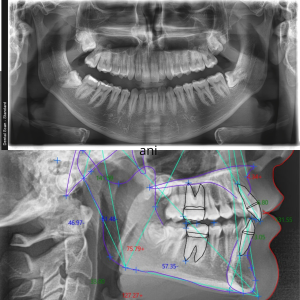

2D snimanje zuba

Ortopan

- Ortopan (ortopantomografija) – panoramska 2D radiografska tehnika koja u jednom snimku prikazuje obe vilice, sve zube i korenove, vilične zglobove i okolne koštane strukture.

Telerendgen

- Lateralni cefalogram (Telerendgen), bočni radiografski snimak glave koji prikazuje prostorne odnose između zuba, vilica i kostiju lica. Koristi se ortodontskoj dijagnostici.